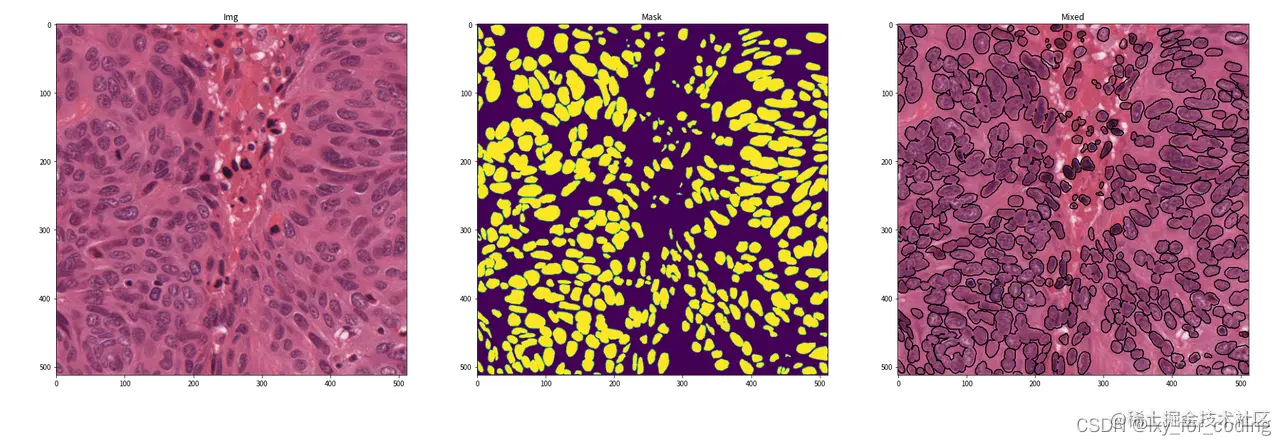

实验数据集示例:

在这里插入图片描述(标注)

在这里插入图片描述

# 获取数据示例并可视化

img, mask = train_data.__getitem__(0)

img, mask = img.mul(255).byte(), mask.mul(255).byte()

img, mask = img.numpy().transpose((1, 2, 0)), mask.numpy().transpose((1, 2, 0))

# 可视化示例

fig, ax = plt.subplots(1, 3, figsize=(30, 10))

ax[0].imshow(img)

ax[0].set_title('Img')

ax[1].imshow(mask.squeeze())

ax[1].set_title('Mask')

ax[2].imshow(img)

ax[2].contour(mask.squeeze(), colors='k', levels=[0.5])

ax[2].set_title('Mixed')